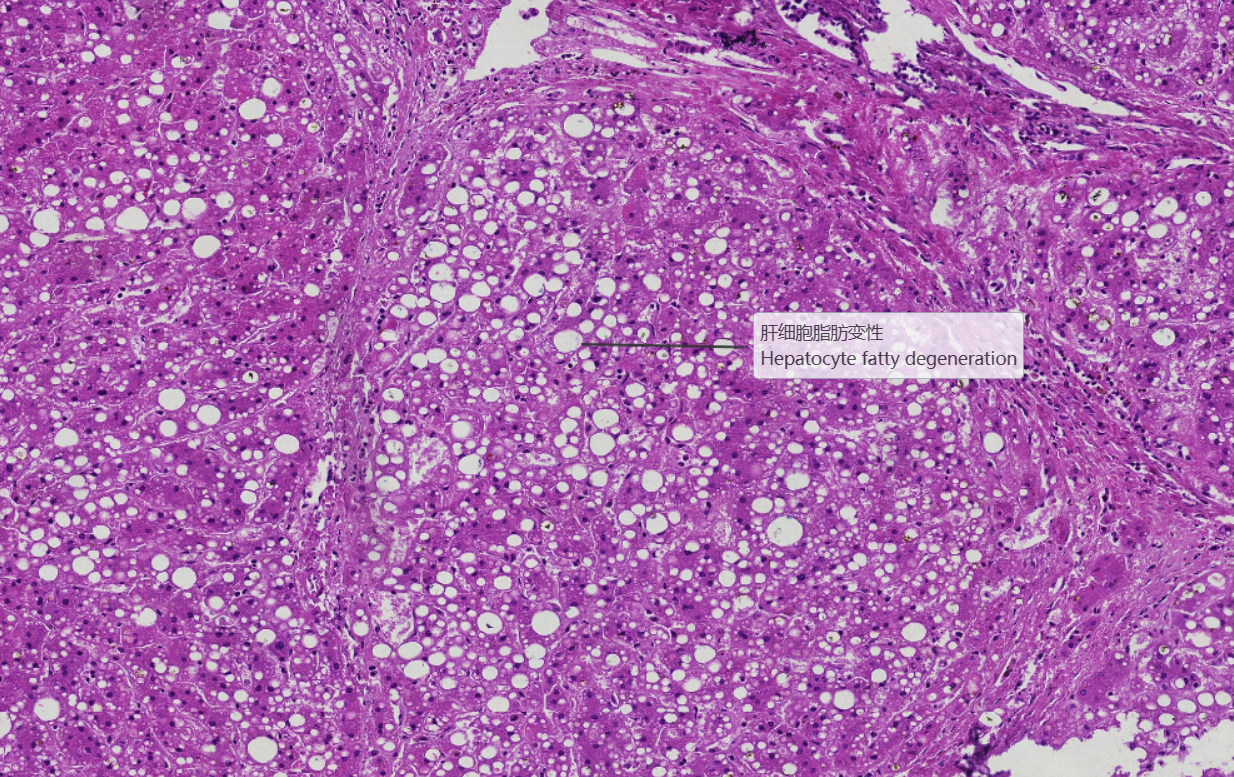

2 坏死后性肝硬化